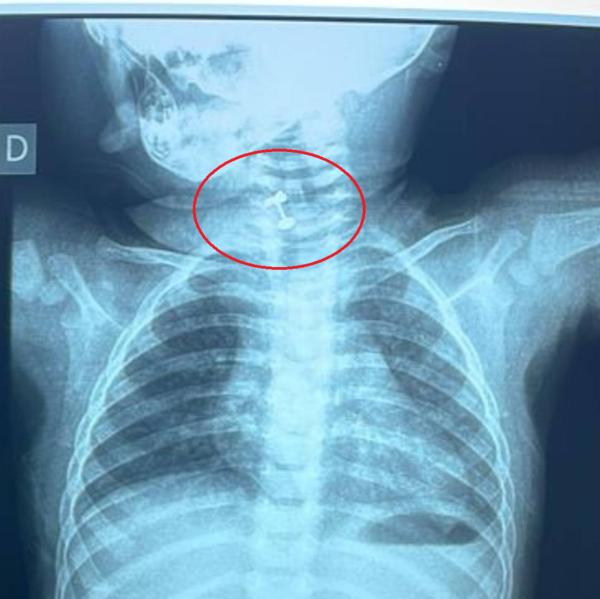

Ineram: salvan a beba de morir asfixiada luego de tragar su arito - trece

Desde el Ineram reportaron que una beba de 10 meses estuvo a punto de morir asfixiada luego de tragar su arito. El objeto extraño pudo ser extraído gracias a la rápida actuación de los médicos. ...[Leer más]